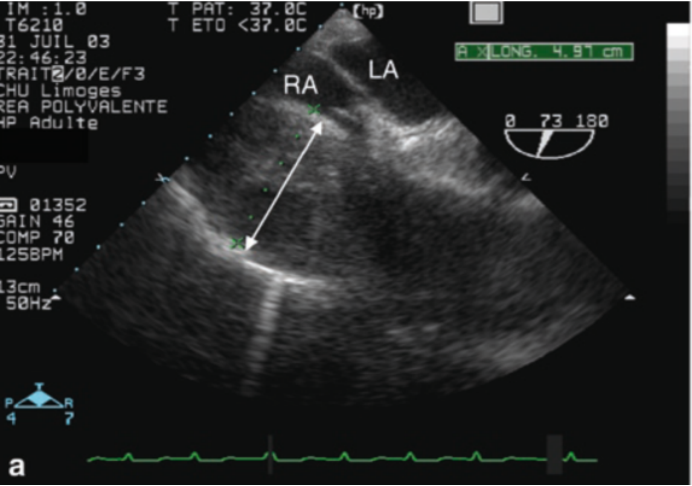

除了上述征象,肺栓塞(急性肺心病)还有其他超声表现:①三尖瓣环收缩期位移(TAPSE)缩小,静脉回流梯度减少(<16 mm,提示右室收缩功能降低)。TAPSE测量方法:M型超声,四腔心切面测量三尖瓣环从舒张末期到收缩末期的纵向位移(图3);正常值≥17 mm。②下腔静脉扩张且吸气时无塌陷(提示右心负荷过重)。③右心室腔内直接探及血栓(特异性高)。

图片

3  TAPSE测量方法